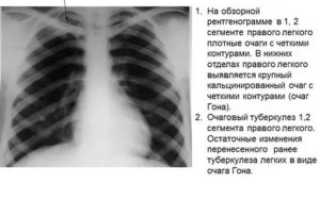

• Очаговые образования представляют собой участки белого цвета на черном фоне (на снимке-негативе). В реальности пораженная область, скорее всего, имеет более темный цвет, чем здоровые ткани легкого.

• Если врач заметит на снимке участки кальцинирования или обызвествления (капсул, пропитанных солями кальция) вокруг очага, это может быть признаком доброкачественности образования. Кальцинаты по цвету похожи на кости скелета, видимые на этом снимке. Такие явления часто обнаруживаются после затяжных простудных заболеваний, бронхитов или уже излечененного туберкулеза и представляют собой некий шрам на легких. Пациента с образованием, на котором заметны признаки кальцината, пульмонологи обычно просят раз в полгода делать контрольные снимки.